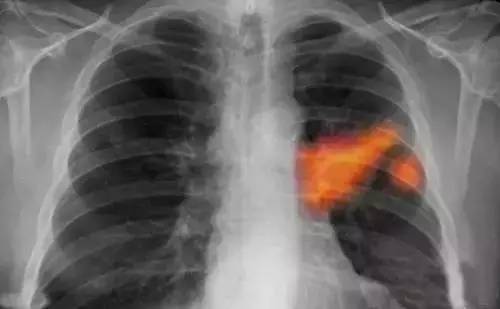

武漢肺癌最新動(dòng)態(tài)顯示,研究、治療和科普工作取得重要進(jìn)展。當(dāng)?shù)蒯t(yī)療機(jī)構(gòu)和專(zhuān)家團(tuán)隊(duì)不斷深入研究肺癌的發(fā)病機(jī)制,采用最新的治療技術(shù),提高患者生存率??破招麄饕布訌?qiáng),提高公眾對(duì)肺癌的認(rèn)識(shí),促進(jìn)早期發(fā)現(xiàn)和治療。這些努力為肺癌患者帶來(lái)希望,展示了武漢在肺癌領(lǐng)域的積極進(jìn)展。

武漢的科研團(tuán)隊(duì)在肺癌的基因組學(xué)研究方面取得了重要突破,某研究團(tuán)隊(duì)成功識(shí)別了數(shù)個(gè)與肺癌發(fā)生、發(fā)展密切相關(guān)的關(guān)鍵基因,這一發(fā)現(xiàn)為肺癌的精準(zhǔn)治療提供了有力支持,該團(tuán)隊(duì)還積極參與臨床試驗(yàn)和新藥研發(fā),與制藥公司緊密合作,推動(dòng)多項(xiàng)針對(duì)肺癌的新藥進(jìn)入臨床試驗(yàn)階段,部分新藥已顯示出顯著的療效,為肺癌患者帶來(lái)了新的希望。

在手術(shù)治療方面,武漢的醫(yī)療機(jī)構(gòu)引入了先進(jìn)的手術(shù)設(shè)備和技術(shù),如機(jī)器人手術(shù)系統(tǒng),通過(guò)這一技術(shù),醫(yī)生和醫(yī)療團(tuán)隊(duì)能夠更精準(zhǔn)、更安全地進(jìn)行肺癌手術(shù),大大提升了手術(shù)成功率,針對(duì)肺癌的綜合治療,武漢的專(zhuān)家團(tuán)隊(duì)積極優(yōu)化治療方案,結(jié)合患者的具體情況,采用免疫治療、靶向治療等新型治療方法,為患者提供更加個(gè)性化的治療方案,某肺癌患者經(jīng)過(guò)綜合治療,成功戰(zhàn)勝病魔的案例便是其中的亮點(diǎn)。